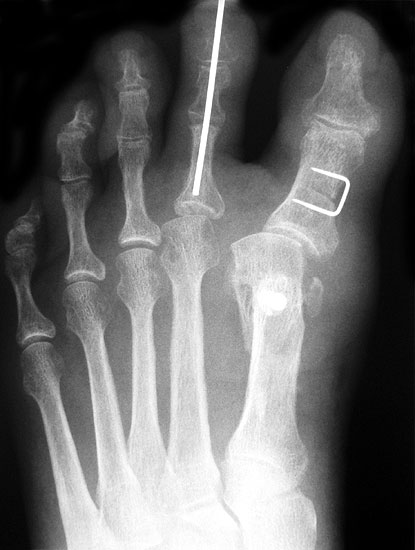

Die dorsoplantaren Röntgenaufnahmen zeigen eine Open-wedge Technik mit der normalerweise ein erhöhter intermetatarsaler Winkel gut zu korrigieren ist (Abbildung 3). Die Wirksamkeit einer Basisosteotomie ist umso größer, je proximaler diese durchgeführt wird. Je weiter distal die Osteotomie, umso geringer die Korrektur. Auf den postoperativen Bildern ist der distal unverändert große Abstand zwischen Metatarsale I und Metatarsale II erkennbar, bei gleichzeitiger Subluxation des Großzehengrundgelenks und dezentrierten Sesambeinen. Darüber hinaus finden sich initiale degenerative Veränderungen im Großzehengrundgelenk. Klinisch bestand eine hohe Weichteilspannung, bei verkürzter Extensor- und Flexor hallucis longus Sehne.  Daher wurde ein verkürzendes Verfahren zur Revision gewählt (Abbildung 4). Die Lapidusarthrodese stellt ein sehr zuverlässiges Verfahren zur Behandlung von Hallux valgus Rezidiven dar 9. Die Fusion des Tarsometatarsale-I-Gelenks kombiniert Stabilität mit einem hohen Korrekturpotenzial. Aufgrund der verfahrensimmanenten Verkürzung des ersten Strahls und der in diesem Fall bereits präoperativ vorhandenen Transfermetatarsalgie wurde die Entscheidung für eine verkürzte Weil-Osteotomie am zweiten bis fünften Strahl gefällt. Die Kombination beider Verfahren führte zu einem homogenen Metatarsale-Index und zu einer gleichmäßigen plantaren Druckverteilung 10. Die Hallux valgus interphalangeus Fehlstellung wurde mit einer Akin-Osteotomie korrigiert.